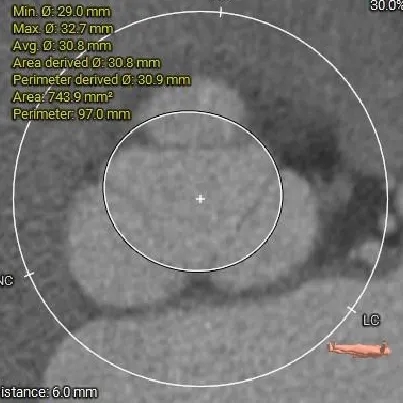

瓣上结构测量

瓣上4mm

29.9mm

瓣上空间逐渐增大,仅瓣上2mm左右可提供锚定